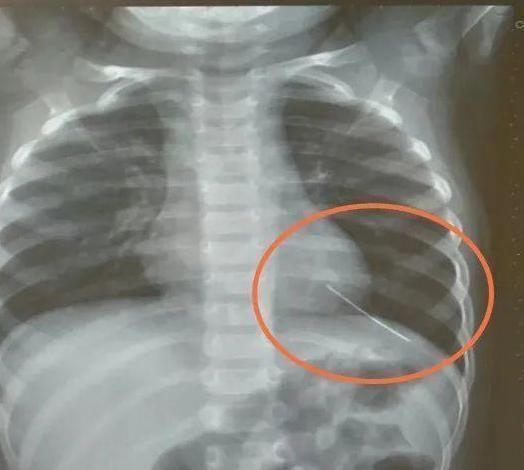

当医生看了一眼X光,医生都很惊讶和害怕,医生说萱萱的胸腔里面有异物,看上去是细长状的,类似一根针,必须马上手术。

为此,医院开设了绿色通道,经过一系列的检查和讨论,确定了长针的位置。如果长针再接着移动下去,很有可能会刺到心脏,到时候孩子就不堪设想了。